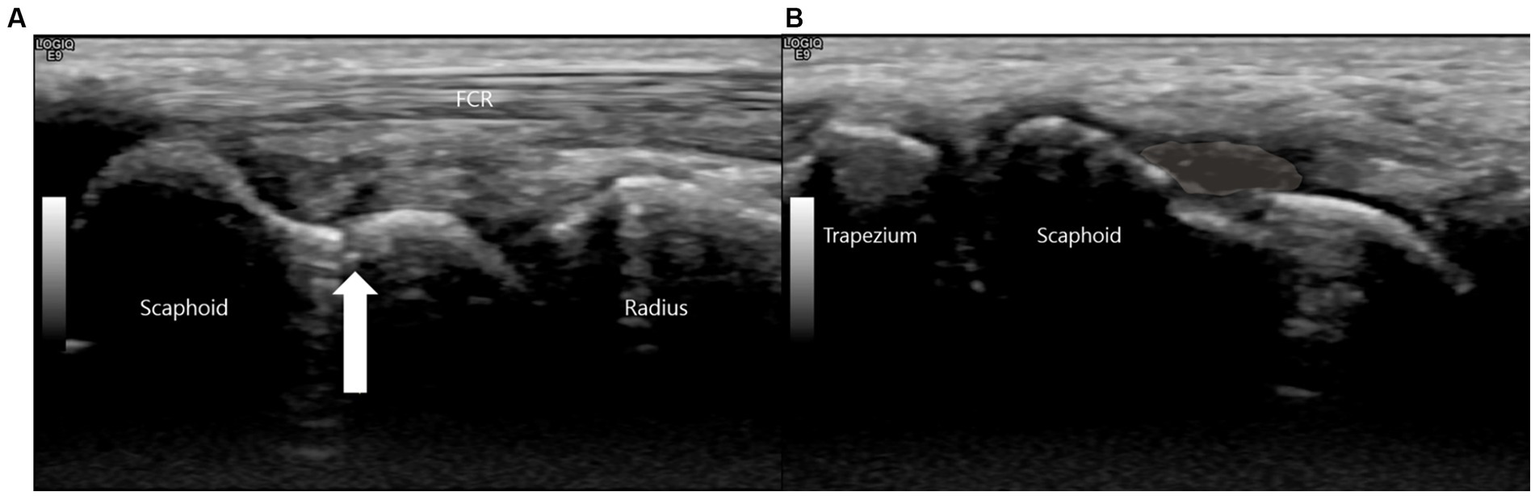

Due to these persistent and highly localized signs, a high-resolution musculoskeletal ultrasound examination was performed at the point of care using a high-frequency linear transducer (18-5 MHz, LOGIQ E9, GE Healthcare). The point-of-care ultrasound examination began with a static assessment. With the wrist in slight ulnar deviation to maximize the longitudinal view of the scaphoid, a clear hypoechoic cortical breach was identified at the scaphoid waist. A small, overlying hypoechoic collection consistent with a hematoma was also noted (Figure 2).

Figure 2

This is a high-resolution ultrasound image of the scaphoid waist. (A) The white arrow indicates the fracture site. (B) A hypoechoic collection consistent with a hematoma (shaded area) is noted superficial to the cortical breach.

This sonographic finding correlated precisely with the point of maximal tenderness elicited during the physical examination, confirming it as the anatomical source of the patient’s symptoms.